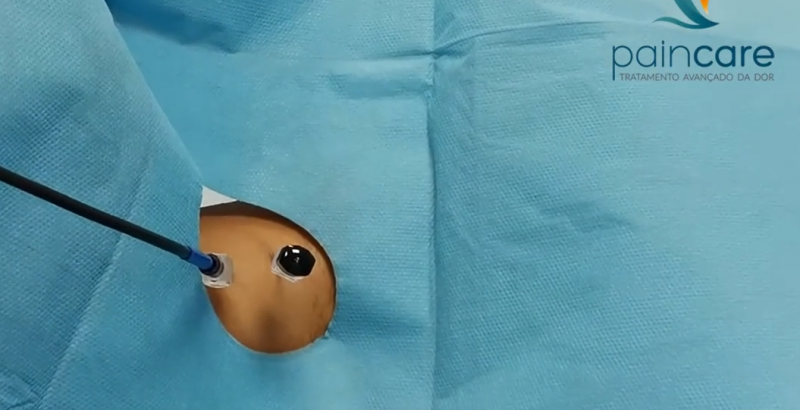

O que é a neuroestimulação? A neuroestimulação é uma técnica médica que utiliza impulsos elétricos de baixa intensidade para modular a atividade do sistema nervoso central e periférico. Ao interferir com os sinais de dor que vão da periferia do nosso corpo para o cérebro, este tratamento oferece um alívio significativo e duradouro para muitas […]